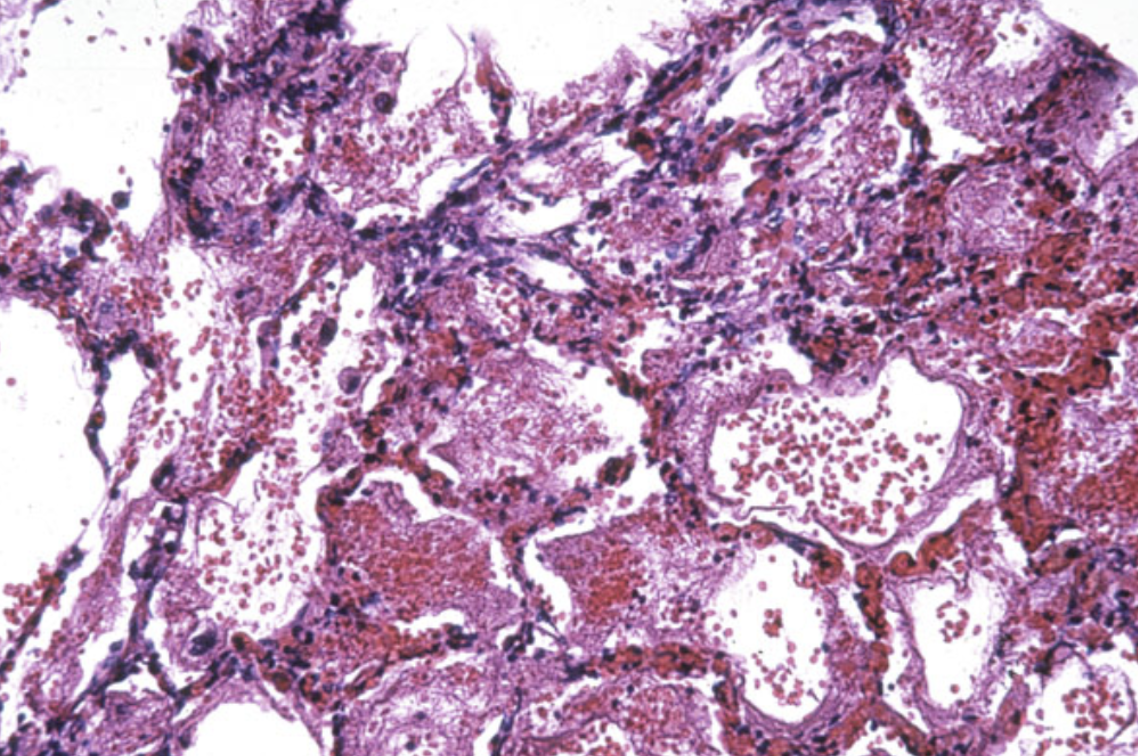

Приготовьтесь разочароваться! Мало того, ветрянка переносится всеми по-разному, так еще и вирус остается в организме на всю жизнь. А если принять во внимание тот факт, что ветряная оспа, как и любая другая болезнь, может иметь неприятные последствия для здоровья, ходить на такие вечеринки не слишком-то сильно захочется! Возможными осложнениями после перенесенного заболевания являются пневмония, бронхит, отиты, энцефалит (воспаление тканей головного мозга, одно из самых частых неврологических осложнений у детей в возрасте до 7 лет [25]). Список неприятных ветряночных последствий дополняют мозжечковая атаксия (нарушение координации движений), менингит (воспаление оболочек головного и спинного мозга), бактериальные кожные инфекции. У взрослых наиболее частым осложнением после перенесенного заболевания становится пневмония (рис. 9) [24], [26]. А у детей с довольно высокой частотой развиваются осложнения со стороны кожных покровов и слизистых (около 65,5%) [27]. Ведь сыпь сопровождается сильным зудом, и перестать ее чесать не так уж просто! В редких случаях у пациентов в возрасте до 18 лет может наблюдаться развитие синдрома Рейе — острой энцефалопатии (невоспалительного заболевания головного мозга) с поражением печени. Как правило, такая патология появляется вследствие приема препаратов ацетилсалициловой кислоты (особенно аспирина) в качестве жаропонижающих и противовоспалительных средств для купирования симптомов лихорадки [28].

Рисунок 9. Кровоизлияние в альвеолах (маленьких пузырьках в легких, где происходит газообмен) при пневмонии, вызванной вирусом ветряной оспы.